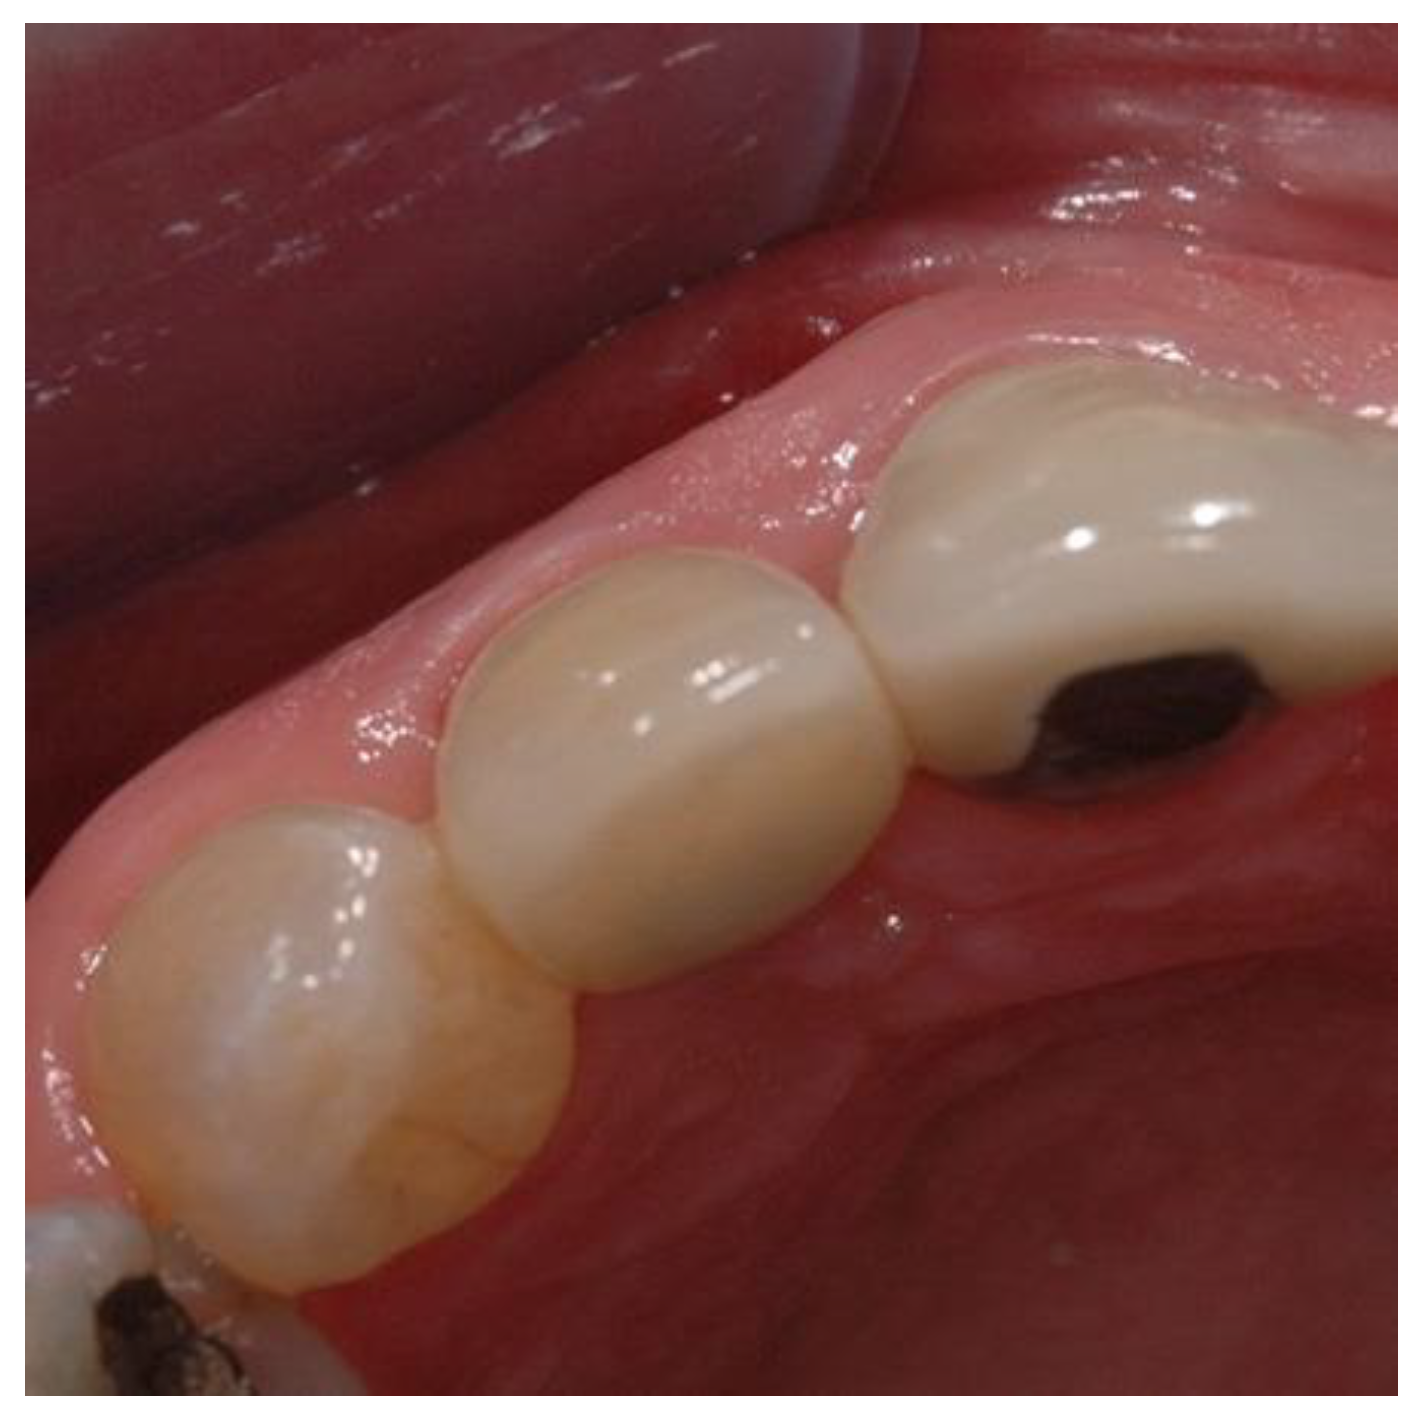

Figure 8. Preoperative image used for PES evaluation.

Preprints 86078 g007